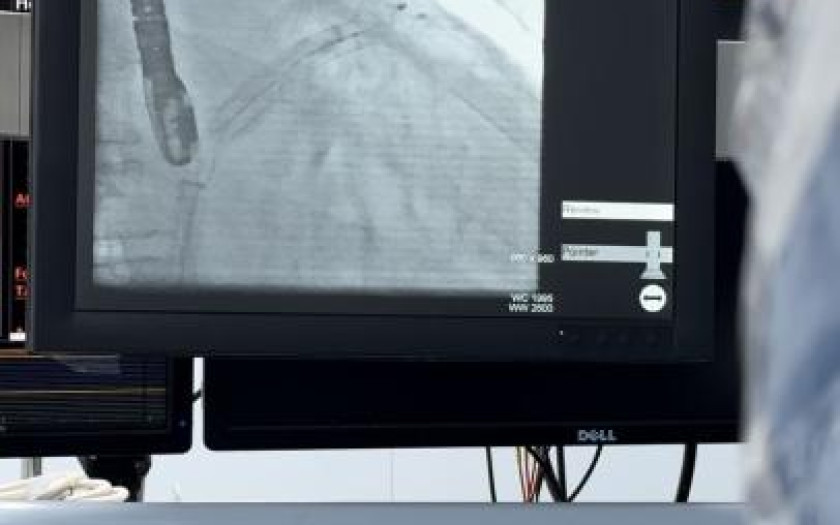

В Научно-исследовательском институте кардиологии и внутренних болезней успешно проведена высокотехнологичная операция по имплантации окклюдера ушка левого предсердия. Сегодня НИИКВБ является единственным медицинским центром в Казахстане, где выполняются такие вмешательства.

По его словам, учитывая жалобы и данные анамнеза, а также высокие ишемические и геморрагические риски, пациентке было рекомендовано проведение рентгенэндоваскулярной окклюзии ушка левого предсердия.